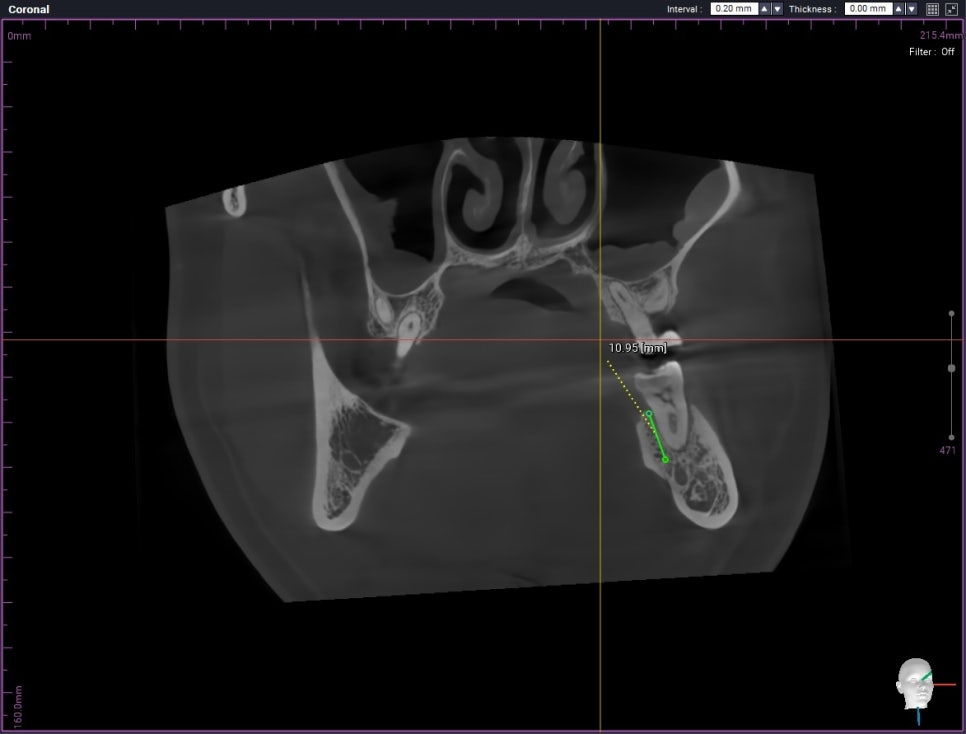

그리고 발치 후 임플란트 식립을 위해

식립 전 CT도 찍어 골 두께와 깊이

그리고 식립 위치를 미리 파악해 줍니다.